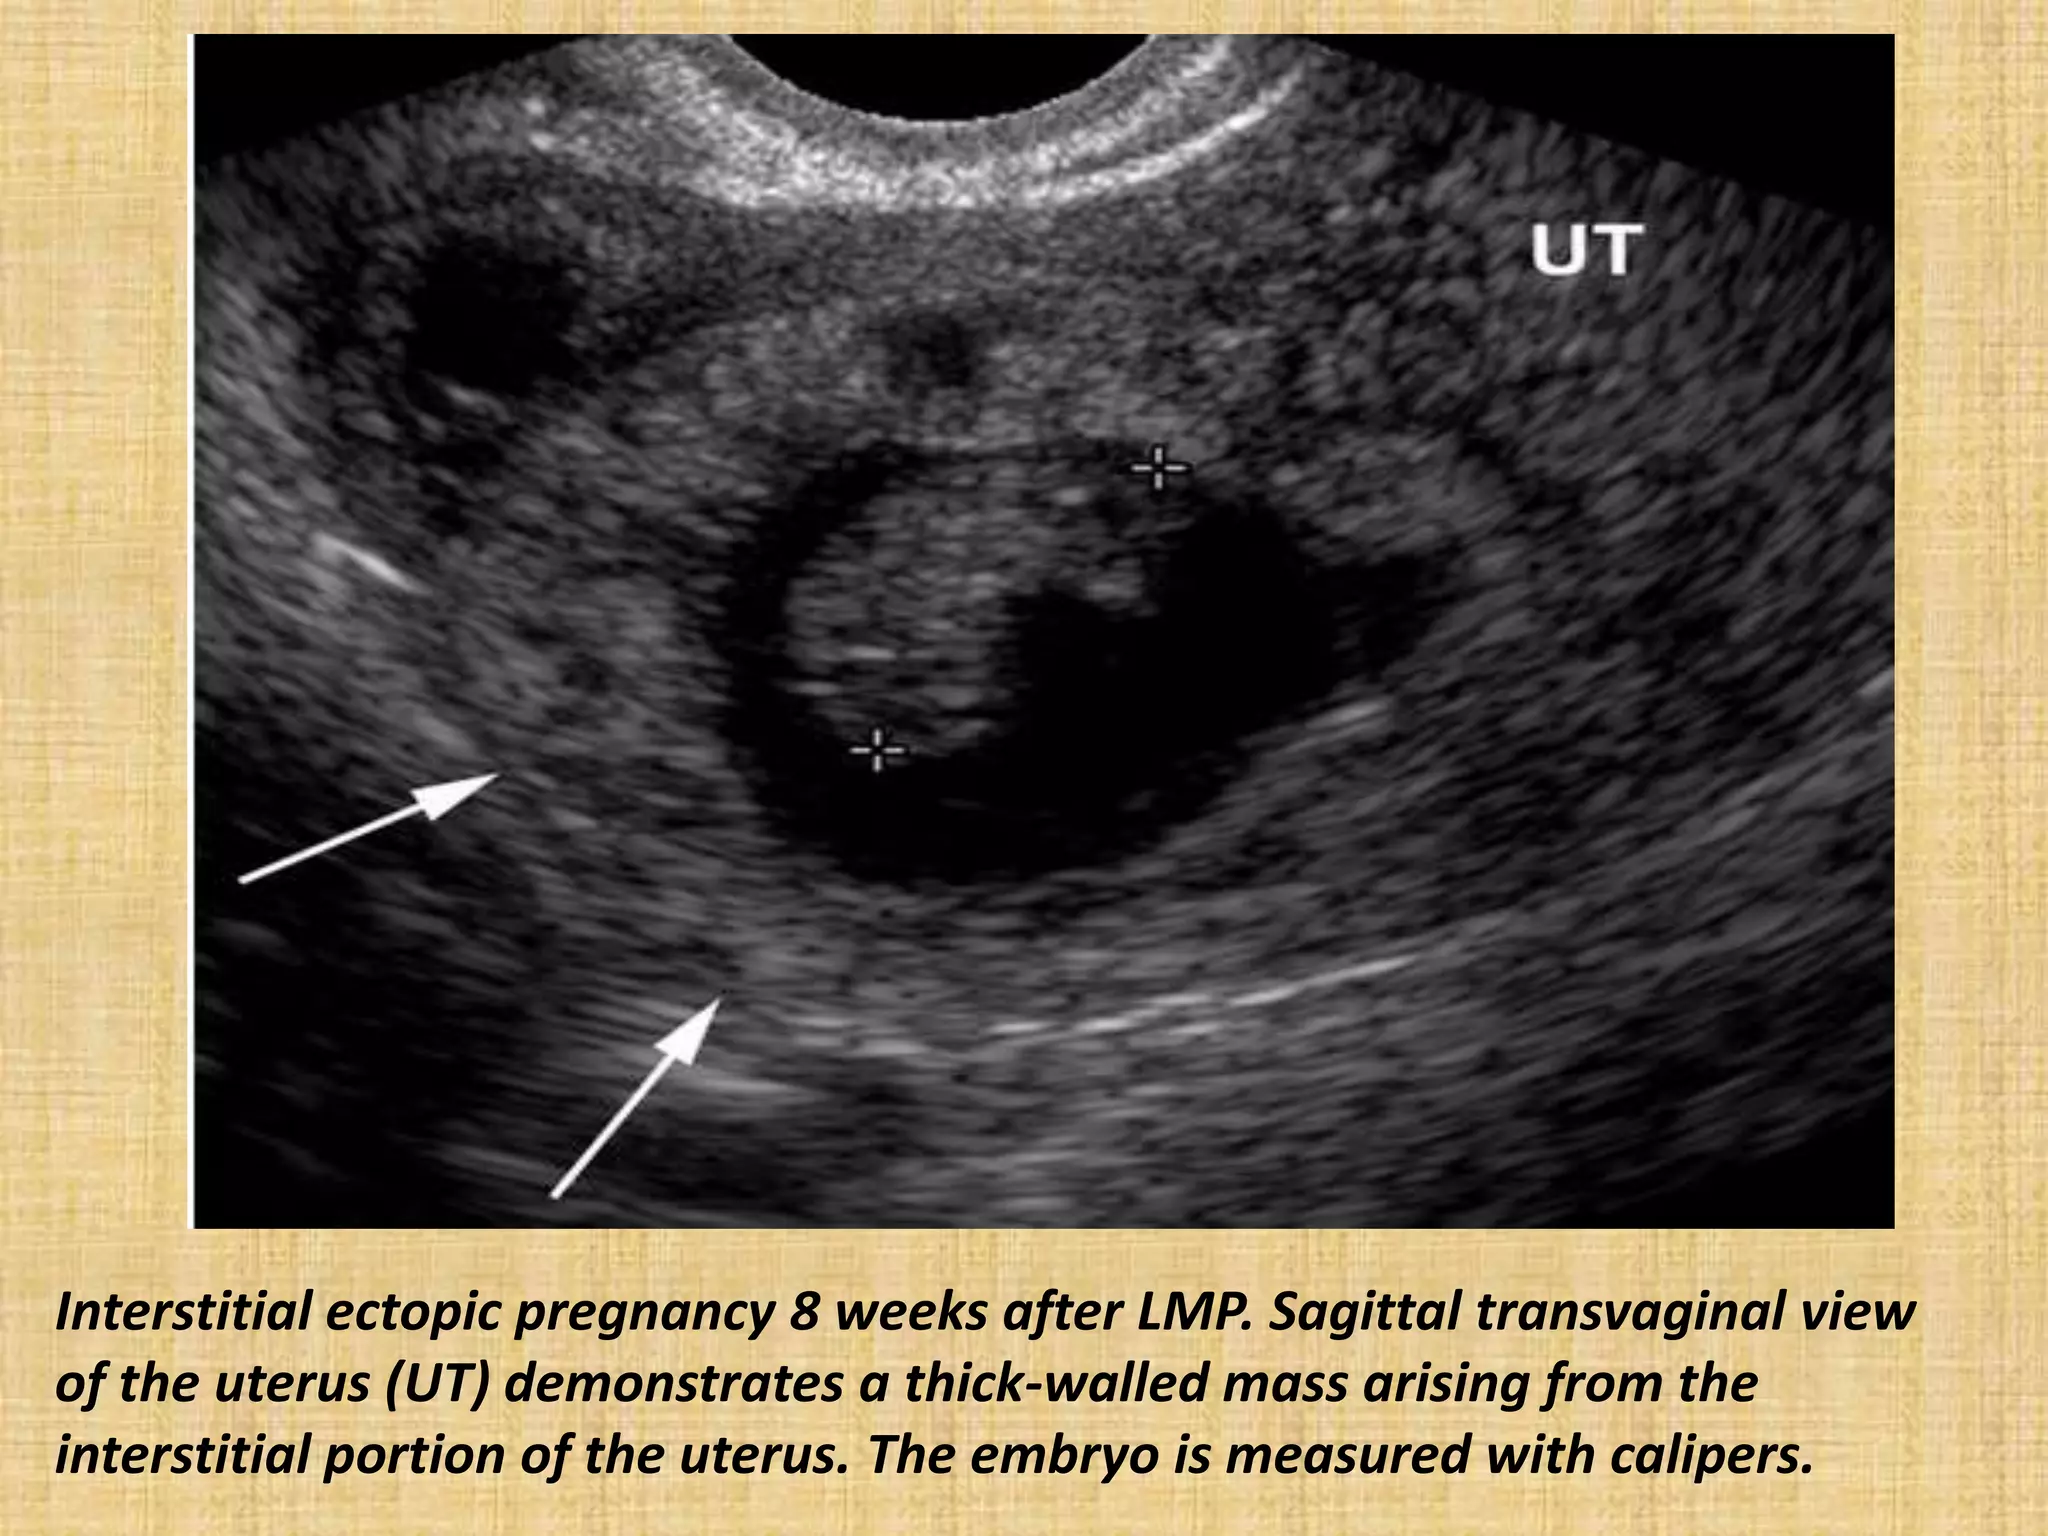

Interstitial ectopic pregnancy 8 weeks after LMP. Sagittal transvaginal view

of the uterus (UT) demonstrates a thick-walled mass arising from the

interstitial portion of the uterus. The embryo is measured with calipers.